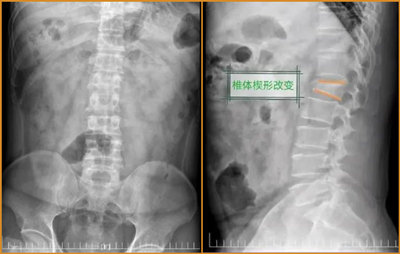

完善相关检查后,接诊医生发现患者因外伤导致腰椎爆裂性骨折,其中一节腰椎骨头碎裂,脊柱严重变形。经番禺区中医院常驻化龙医院脊柱外科专家刘伯昊主任会诊后,诊断为第一腰椎爆裂性骨折,椎体高度下降2/3以上,脊柱明显出现了“驼背”,情况较为严重。

“患者骨折处的部分碎骨片已触碰到神经,若锋利的碎骨片对神经造成损伤,则会导致瘫痪、下肢活动不灵、大小便功能障碍等。手术治疗作为腰椎爆裂性骨折后的最佳选择,可以将塌陷的腰椎复位,矫正脊柱后凸畸形,重新固定起来。如果不进行手术,在骨头正常愈合,神经没有受损的情况下,也会存在驼背,难以久站、久坐,不能做重活等情况。”刘伯昊主任表示。

手术前 手术后